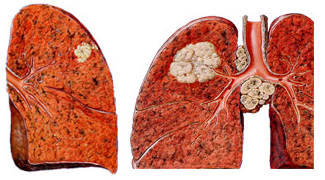

폐암은 폐 조직에서 발생하는 악성 종양으로, 기관지 내 상피세포에서 시작되는 경우가 대부분입니다. 크게는 비소세포폐암(약 85%)과 소세포폐암(약 15%)으로 구분되며, 병리학적 특징과 치료 방법이 다릅니다. 폐암은 국내 암 사망 원인 1위를 차지하고 있으며, 조기 발견이 어려워 진단 당시 이미 전이가 진행된 경우가 많습니다.

⑤ 조직검사 및 생검

CT나 내시경 유도하에 조직을 채취하여 폐암 여부와 종류를 확진합니다.